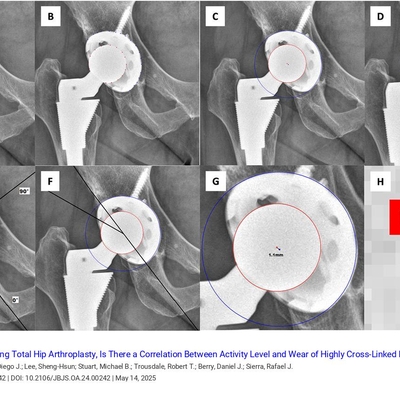

J Bone & Joint Surg

Click on an image below to view more info.